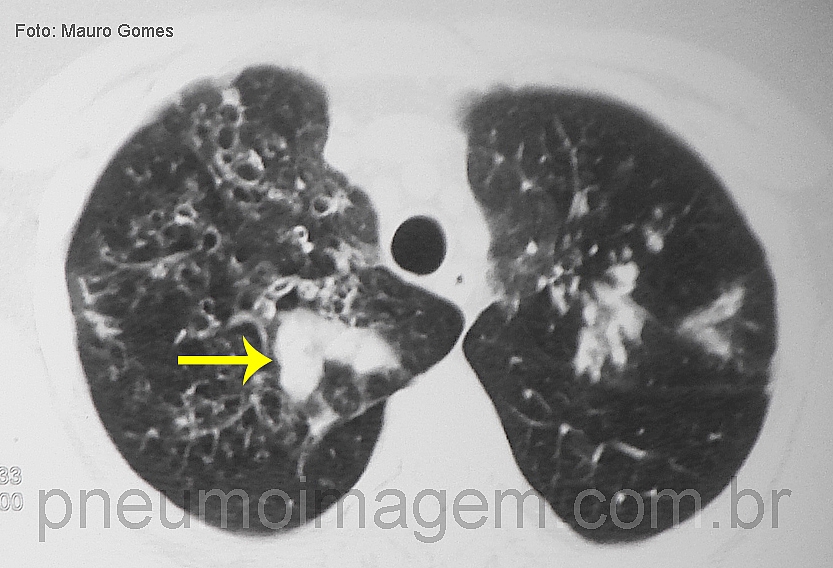

CASO CLÍNICO #22Qual o nome desse sinal e o que ele significa? Deixe seus comentários abaixo.

What is the name of the sign and what it means? Leave your comment below.

a imagem mostra o sinal do dedo de luva, que juntamente com as bronquiectasias, sugerem ABPA